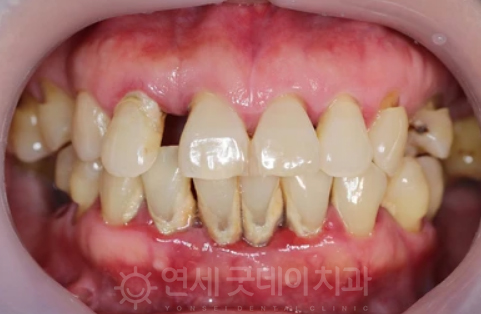

CASE 2 - 치주판막수술

치주판막수술 치료과정

위는 치주판막수술 사례입니다. 일반적으로

주판막수술은 심한 염증으로 치주조직이

광범위하게 파괴된 경우에 시행되거나 골파괴가

복잡해 기구가 접근하기 힘들 시 진행하게 됩니다.

우선 부분마취 후 잇몸을 열어 치아 주변 조직을

분리하여 시술 부위를 직접 확인하면서 염증을

제거하게 되는데요. 모든 치료가 완료되면 잇몸을

다듬어 칫솔질하기 유리한 형태로 만들어드립니다.

이 치주판막수술은 치주건강을 유지하고

치주질환의 진행을 멈추거나 예방하는데

중요한 역할을 맡고 있기 때문에 수술 후에도

적절한 치주 관리와 주기적인 치과 검진이 필요합니다.